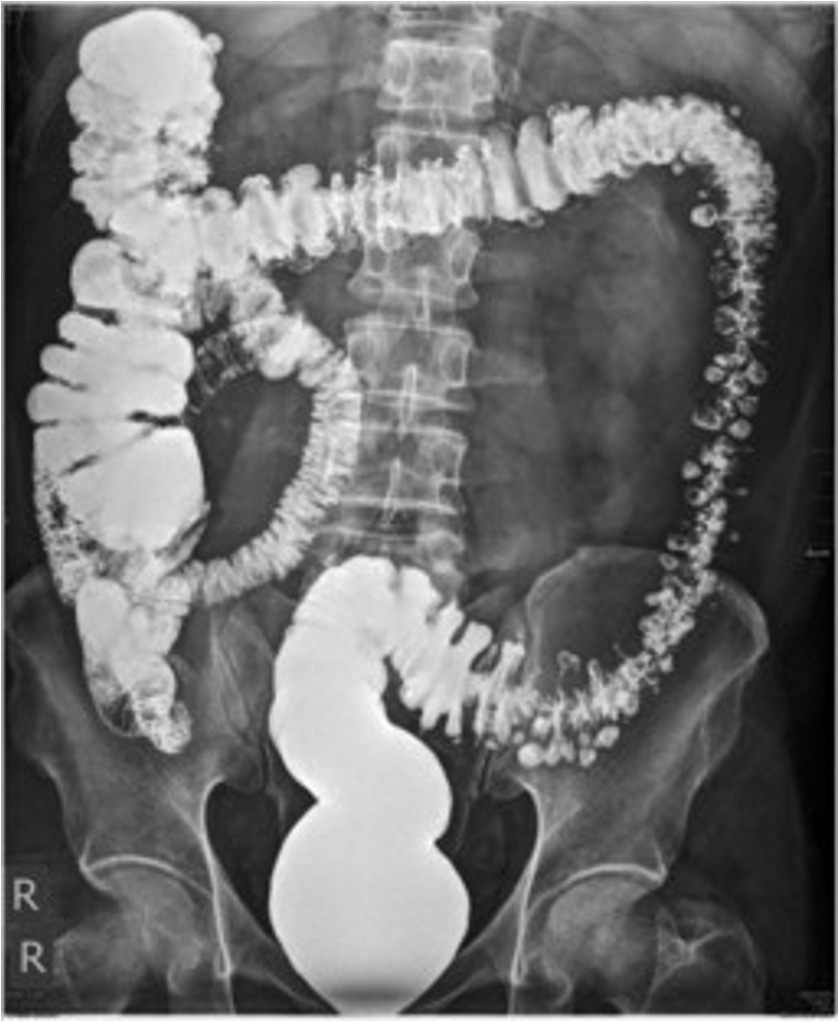

Sigmoid volvulus

Sigmoid volvulus ## Footnote dilation causes the classic coffee-bean sign, a pathognomonic of sigmoid volvulus.